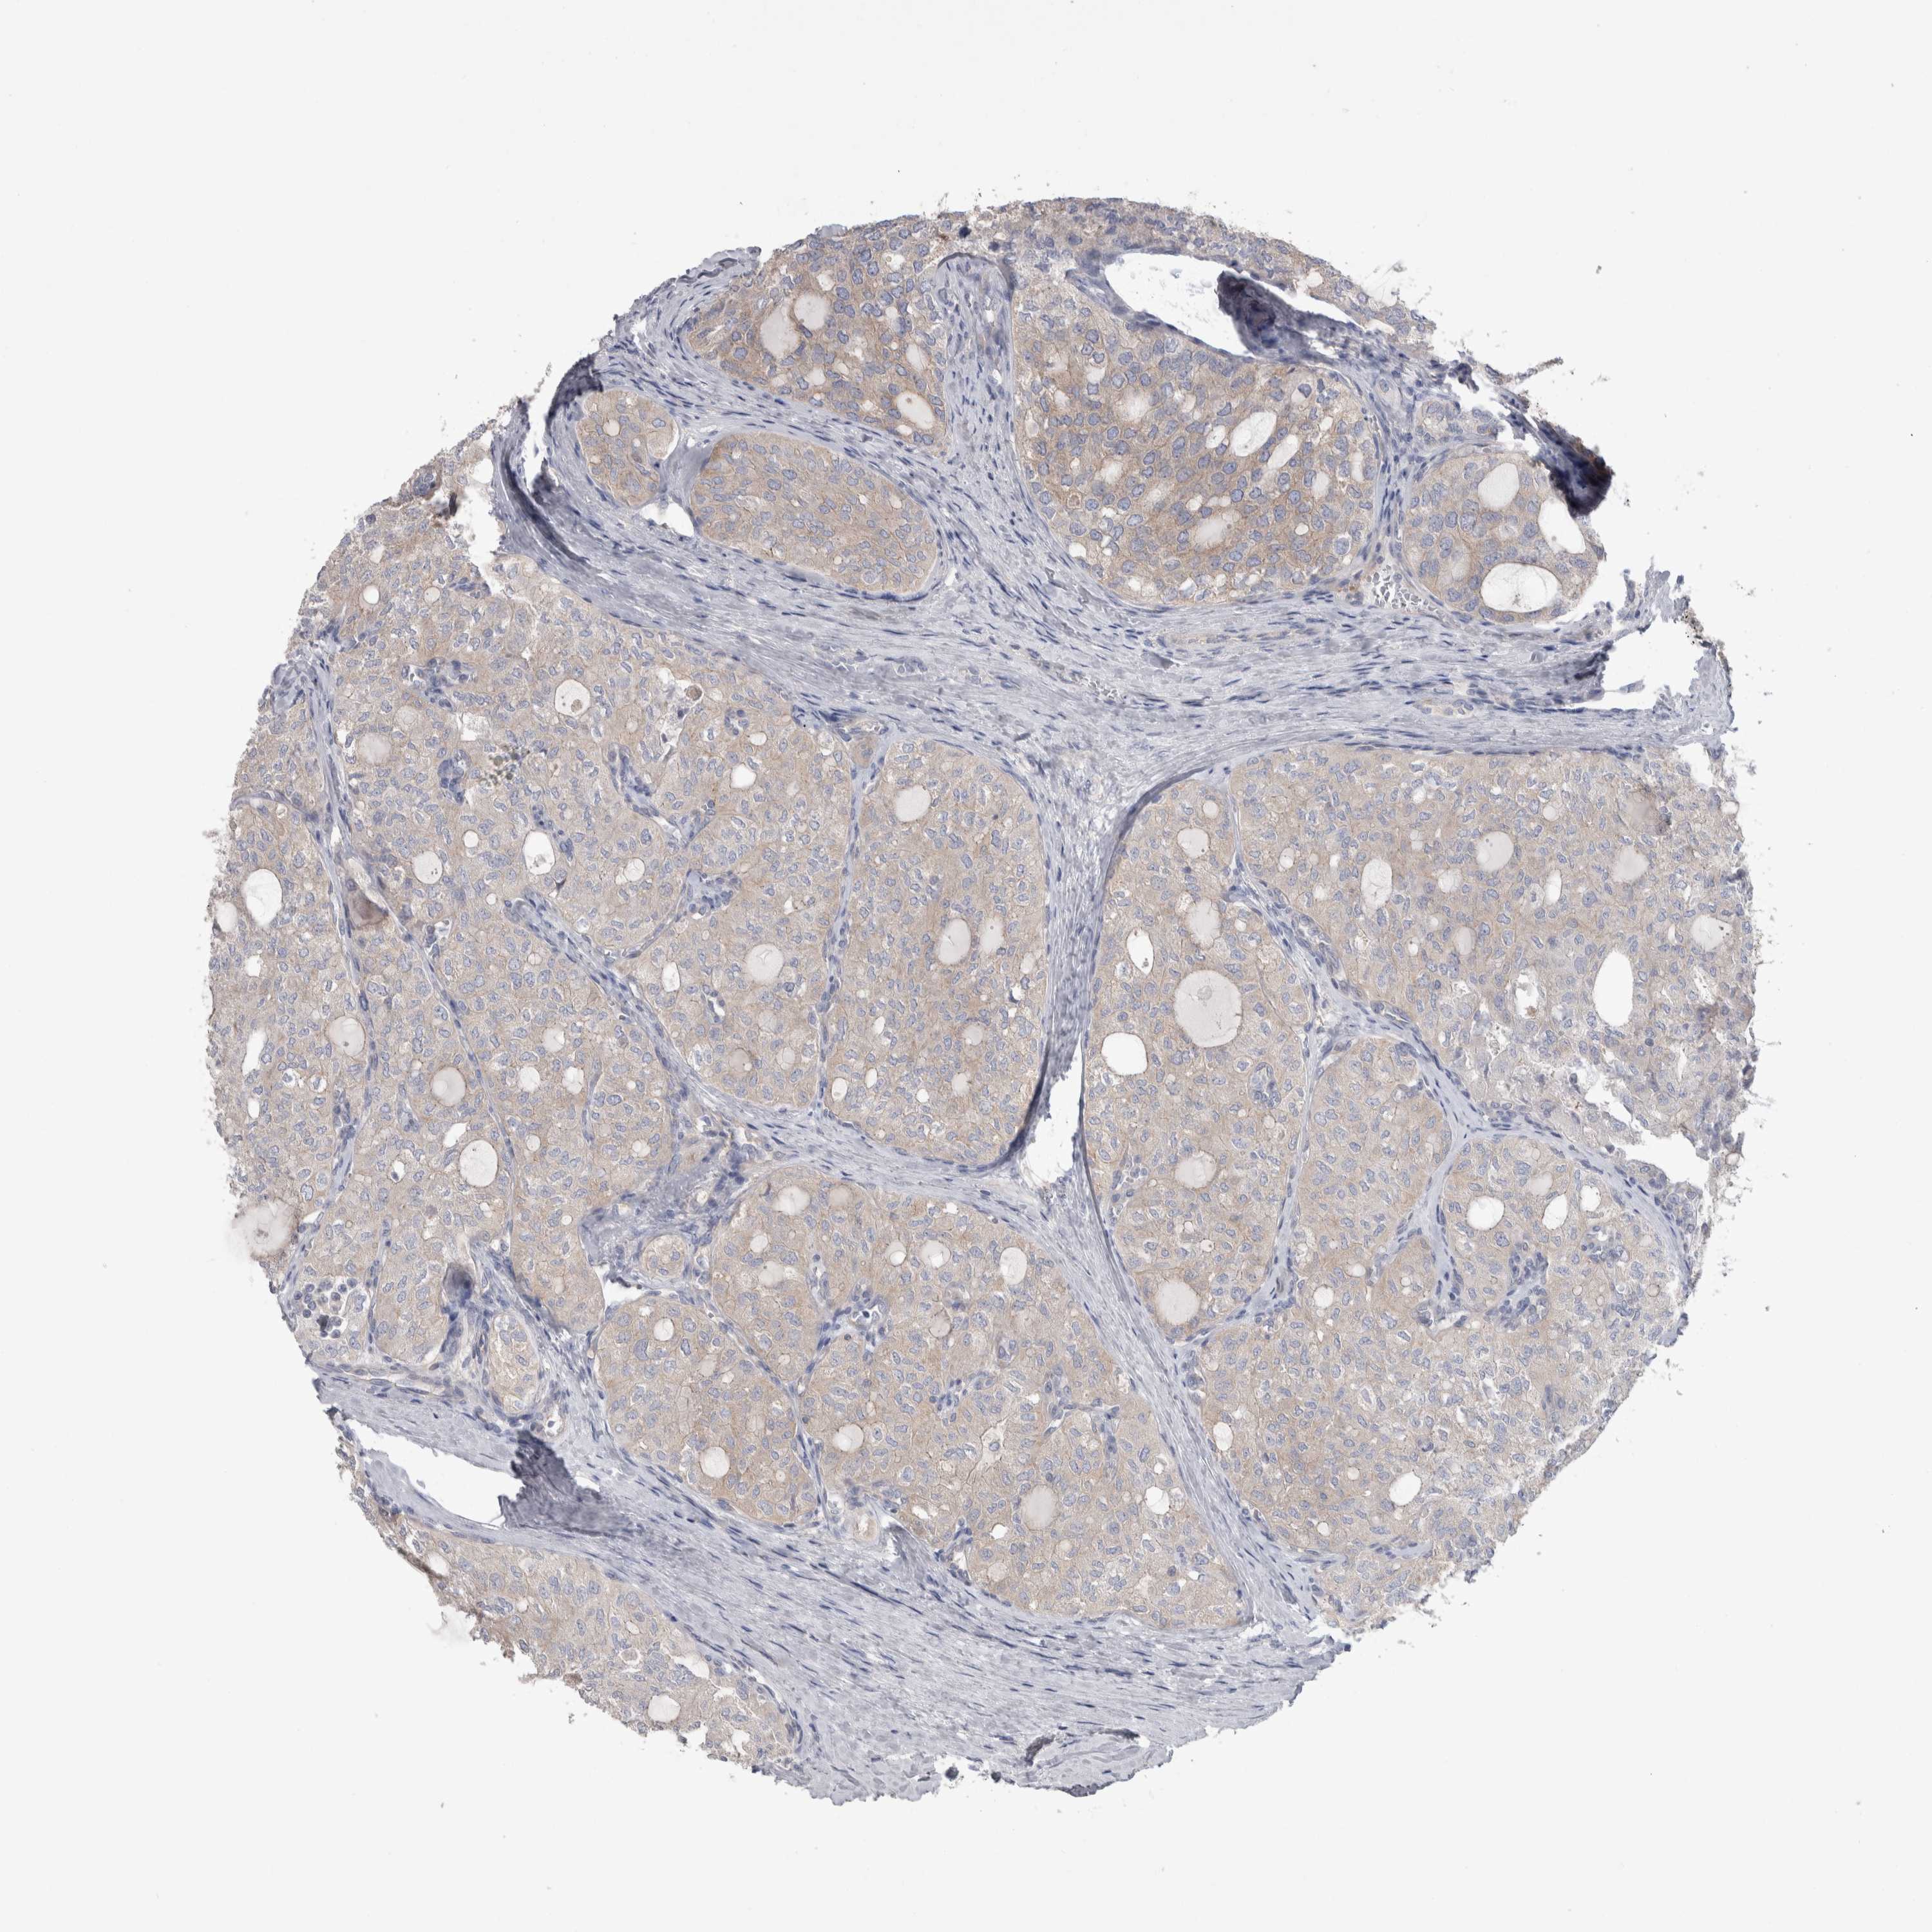

THYROID CANCER - Protein expressioni

A mouse-over function shows sample information and annotation data. Click on an image to view it in a full screen mode. Samples can be filtered based on level of antibody staining by selecting one or several of the following categories: high, medium, low and not detected. The assay and annotation is described here.

Note that samples used for immunohistochemistry by the Human Protein Atlas do not correspond to samples in the TCGA dataset.

Antibody stainingi

Antibody staining in the annotated cell types in the current human tissue is reported as not detected, low, medium, or high, based on conventional immunohistochemistry profiling in selected tissues. This score is based on the combination of the staining intensity and fraction of stained cells.

Each image is clickable and will lead to virtual microscopy that enables deeper exploration of all samples and also displays staining intensity scores, fraction scores and subcellular localization as well as patient and tissue information for each sample.

Antibody HPA003116

Antibody HPA024694

Antibody CAB004419

Staining

High

Medium

Low

Not detected

Intensity

Strong

Moderate

Weak

Negative

Quantity

>75%

75%-25%

<25%

None

Location

Nuclear

Cytoplasmic/membranous

Cytoplasmic/membranous,nuclear

Carcinoma, NOS

Follicular adenoma carcinoma, NOS

Papillary adenocarcinoma, NOS